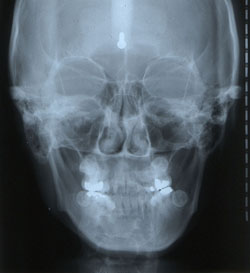

안면비대칭은 왜 생기는가. 여러 가지 선천적 또는 후천적 원인에 의해 한쪽 과두가 과성장 또는 열성장을 하게 되면 비대칭이 나타나는 것으로 알려져있다. 그러나 안면비대칭환자의 모두가 과두성장 차이로 초래되지는 않는다. 과다한 편측저작을 오래 할 경우 저작측의 하악골은 low angle 양상을, 비저작측은 high angle 양상을 초래하여 안면비대칭이 나타나기도 한다. 협소한 상악골에 의해 또는 교합간섭으로 인해 하악골이 편위되는 경우에도 비대칭이 초래될 수 있다. 과두의 성장차이나 이부의 편위 없이 하악골 윤곽이 좌우 다른 경우에도 비대칭적인 안모가 초래될 수 있다. 안면비대칭의 원인에 따라 이에 대한 치료가 결정되므로 안면비대칭 환자에서는 원인파악이 매우 중요하다. 저자는 안면비대칭을 RM, RA, M, 그리고 B type의 4가지로 구분한 바 있으며 이는 정모두부방사선사진 상에서 Ag의 수직위치를 통한 좌우 ramus length 차이와 Me 편위 정도 등에 의해 비교적 간단하게 감별될 수 있음을 소개하였다(그림 1).3,4

그림 1. 안면비대칭의 분류. 안면비대칭은 ramus length의 좌우차이 여부나 Me의 편위 여부에 따라 RM, RA, M, B type으로 구분되는데 이는 정모두부방사선사진에서 쉽게 진단될 수 있다.

·RM (Ramus Menton) type: 편측 ramus 길이가 더 길고 menton은 반대편으로 편위되어 있는 경우로 가장 일반적인 안면비대칭 유형이다. 가능한 원인으로 unilateral condyle hyperplasia, hemifacial microsomia, condyle fracture, condyle ankylosis 등이 있고 대부분 수술교정이 필요하다.

·RA (Ramus Angle) type: 편측의 ramus 길이가 더 긴 반면, menton은 대개 정상범주에 위치한 경우로, 교합상실, 불량 보철물, 교합방해 등의 원인으로 편측저작이 지속되면서 저작측은 low angle, 비저작측은 high angle로 발달해 편측 근육비대, 편측 하악골비대를 나타내는 경우이다. 편측저작 습관을 개선하는 것이 치료에 도움이 된다.

·M (Menton) type: ramus 길이는 좌우 동일하고 menton의 편위만 나타난 경우로 하악골 자체의 비대칭 없이 하악골의 functional shift로 인해 초래된다. 대개 어린이에서 뚜렷하고 성인으로 성장하면서 RM 또는 RA type으로 발전하기도 한다. 성장기 아동에서는 functional shift의 원인을 제거하면 되지만 성인에서는 심한 경우 외과적 치료가 필요하다.

·B (Bulkiness) type: 좌우 ramus 길이가 동일하고, menton의 편위도 없는 상태에서 하악골 하연 shape이나 하악골 부피의 좌우 차이로 인해 비대칭 양상을 보이는 경우로 dental asymmetry는 없으므로 특별한 치료가 요하지 않으나 환자가 원한다면 plastic surgery를 통해서 안면비대칭을 개선할 수 있다.